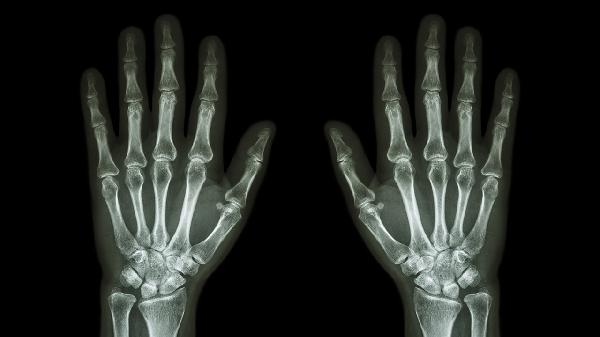

如果关节胀痛持续不缓解或伴有红肿发热、晨僵超过1小时、关节变形等症状,应及时就医。医生可能会建议进行血常规、尿酸检测、类风湿因子检查或X线、核磁共振等影像学检查,以明确诊断是否为骨关节炎、类风湿关节炎或痛风等疾病,并根据检查结果制定针对性治疗方案。